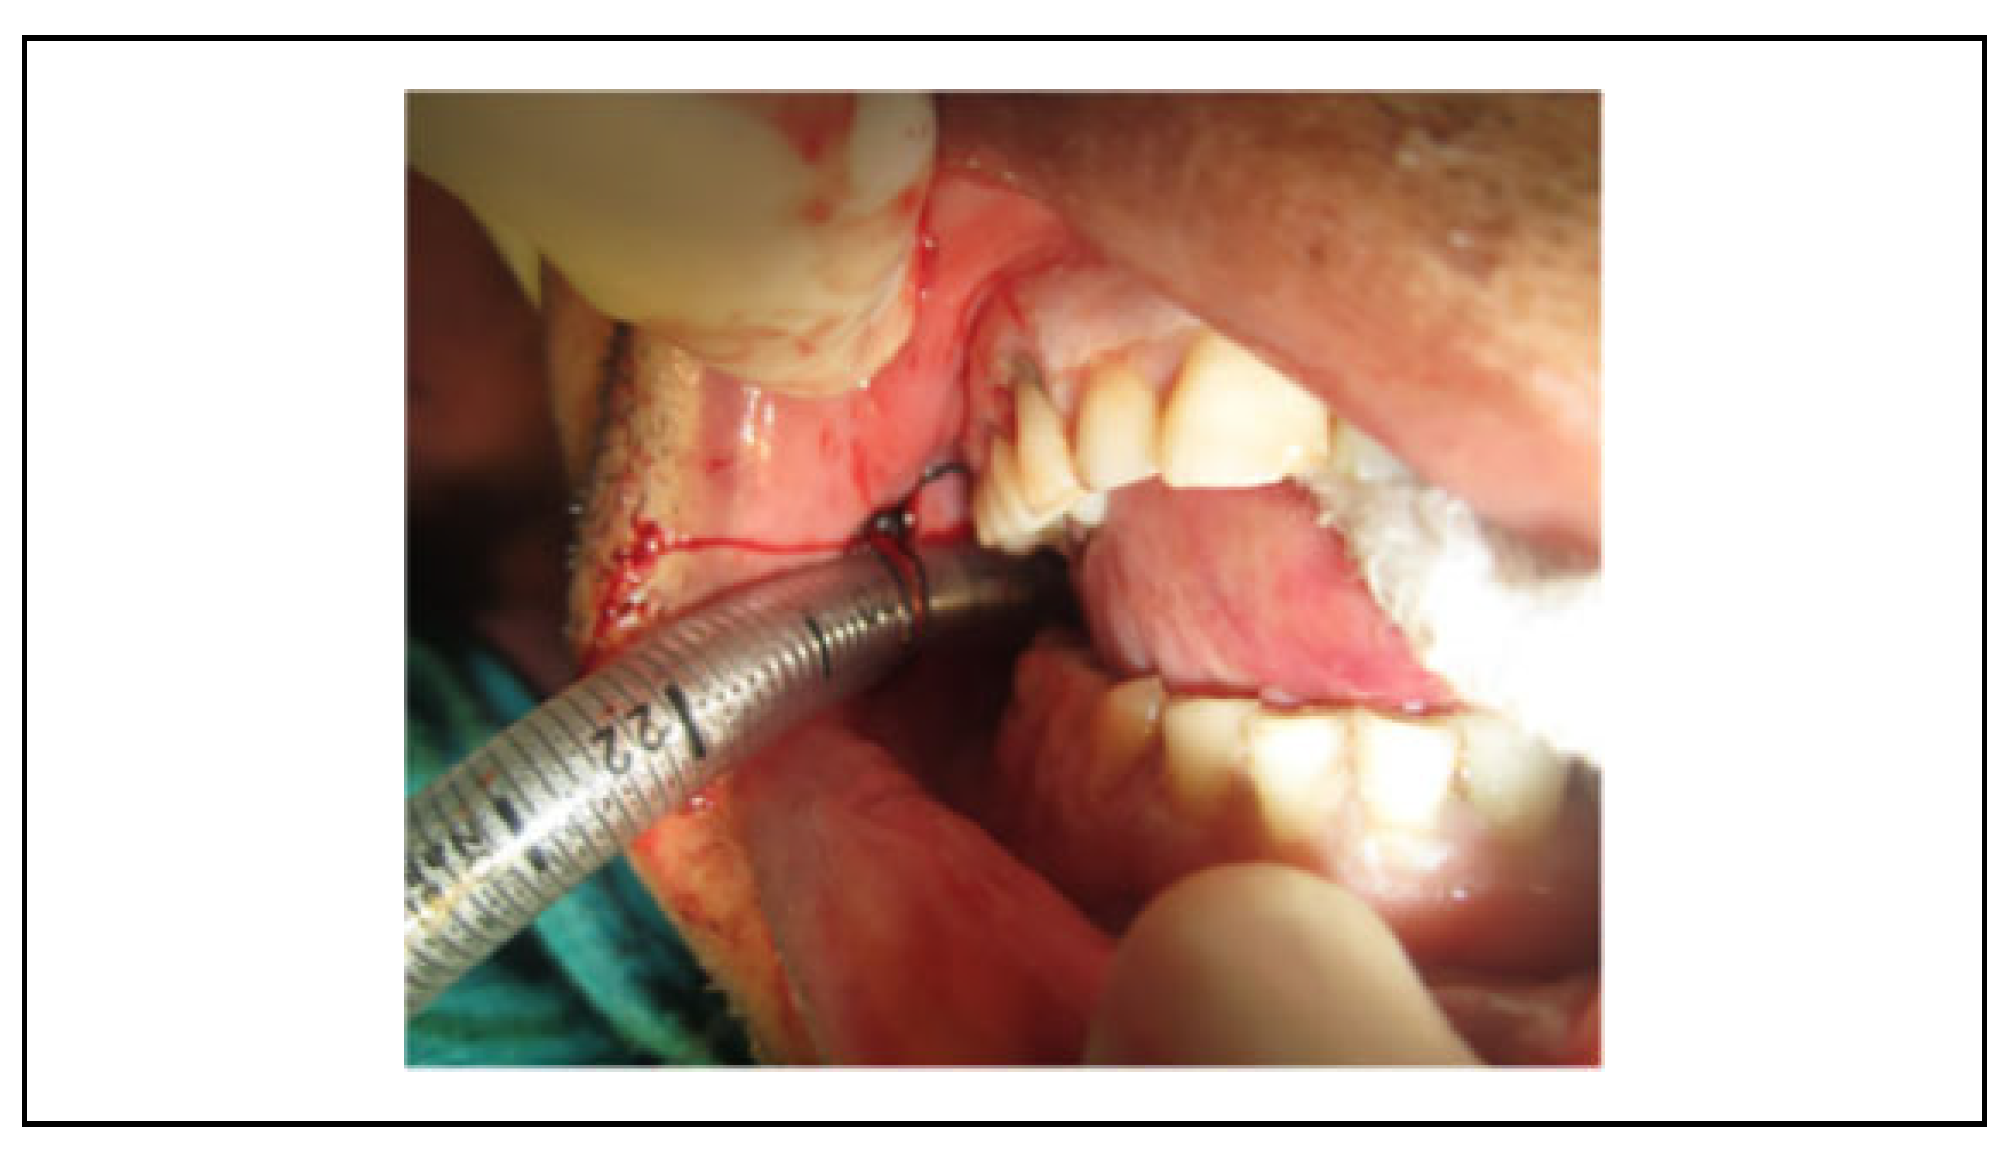

This is a surgical airway obtained by an incision in the submental region and into the floor of the mouth. The oral endotracheal tube is passed through this small incision in the submental triangle.[30] The tube can be secured by suturing it through subcutaneous tissue at the exterior incision site or intraorally through the buccal mucosa or circumdentally (Figure 8).

Figure 8.

Demonstration of submental intubation with endotracheal tube secured to the skin at the exterior incision site with a 3-0 silk purse-string suture.